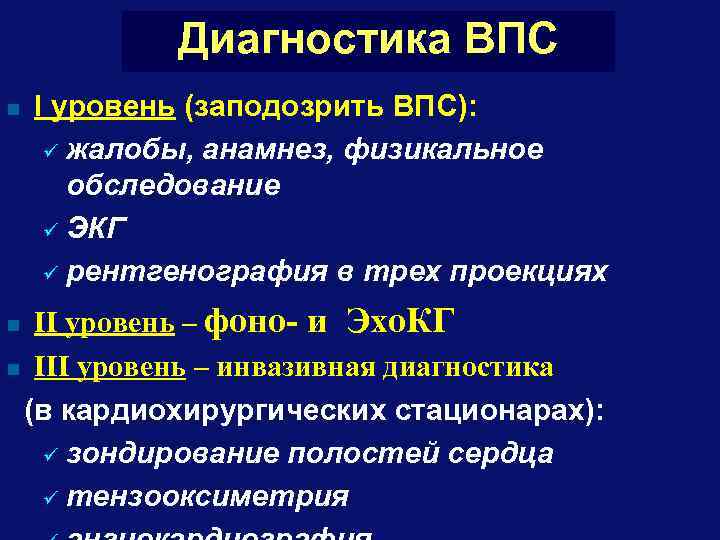

Диагностика ВПС n I уровень (заподозрить ВПС): ü жалобы, анамнез, физикальное обследование ü ЭКГ ü рентгенография в трех проекциях II уровень – фоно- и Эхо. КГ n III уровень – инвазивная диагностика (в кардиохирургических стационарах): ü зондирование полостей сердца ü тензооксиметрия n